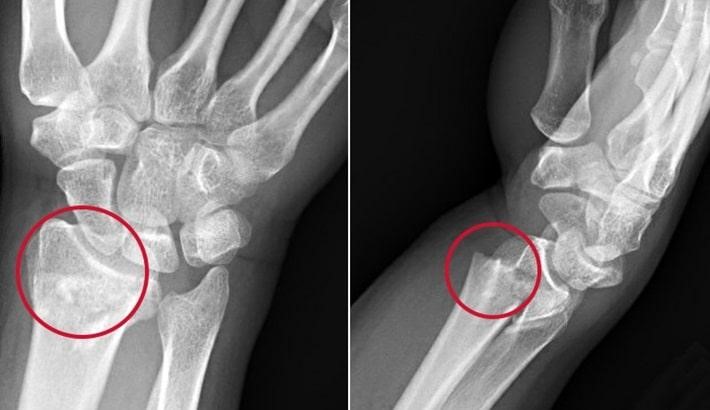

شکستگی‌های داخل مفصلی؛ چرا نیاز به بازسازی دقیق دارند؟

وقتی شکستگی وارد سطح مفصل مچ دست شود، دقت در بازسازی اهمیت بسیار بالایی دارد. حتی یک ناهمواری کوچک (بیش از ۲ میلی‌متر) می‌تواند موجب سایش غیرطبیعی مفصل، درد مداوم، کاهش دامنه حرکتی و آرتروز زودرس شود. در بسیاری از این موارد، تنها راه‌حل مؤثر، جراحی با جااندازی باز و تثبیت با پیچ و پلاک است تا سطح مفصل کاملاً صاف و طبیعی بازسازی شود. برای برنامه‌ریزی دقیق جراحی، گاهی از سی‌تی اسکن استفاده می‌شود تا محل و تعداد قطعات شکستگی به‌خوبی مشخص شود. اگر درمان صحیح صورت نگیرد، بیمار در آینده دچار مشکلات مزمن خواهد شد و حتی ممکن است به جراحی‌های پیچیده‌تر مانند تعویض مفصل یا فیوژن (خشک کردن مفصل) نیاز پیدا کند.

شکستگی‌های داخل مفصلی